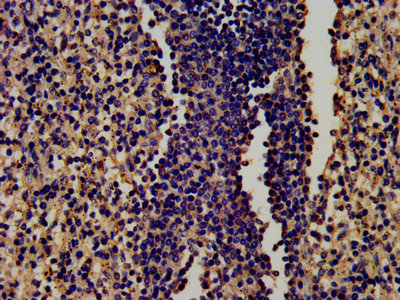

ApplicationELISA, IHC, IF; Recommended dilution: IHC:1:200-1:500, IF:1:50-1:200